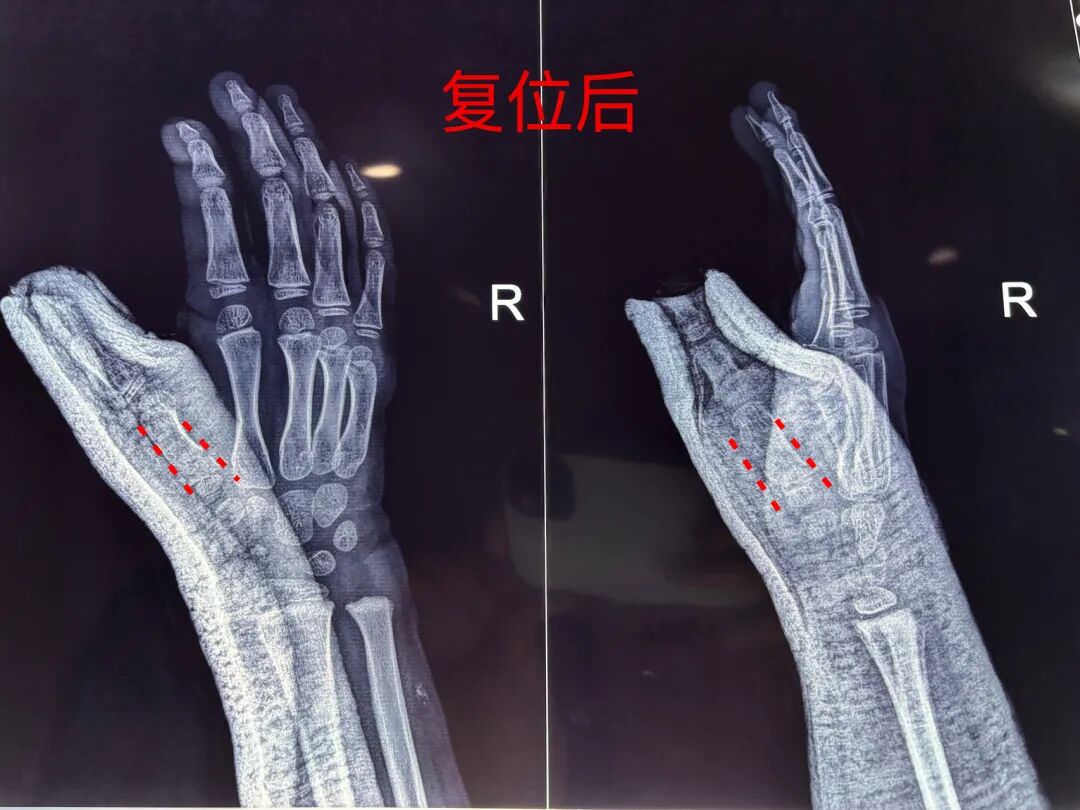

患儿骑自行车时摔倒致拇指受伤,拇指活动受限:拇指无法正常完成外展、主动、被动活动受限。